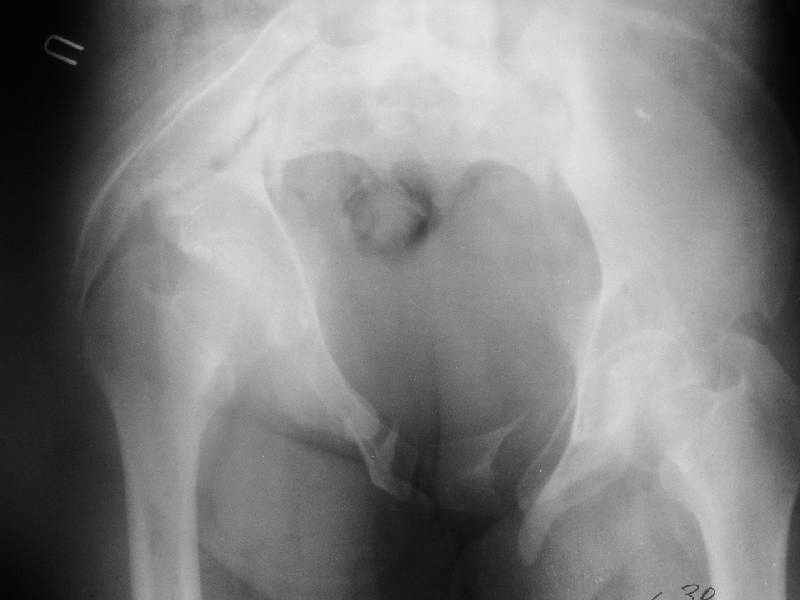

Дополнительно сообщаю, что больную беспокоят боли в области левого крестцово-подвздошного сочленения, в области правого болей нет. Кроме того, беспокоит укорочение конечности (ходит с компенсацией) без дополнительной опоры (в помещении), нарушение осанки (сколиоз, избыточный поясничный лордоз), боли в пояснице, невозможность стоять более 20-30 минут, спать без резинового круга под крестцом и подушкой под коленями, неудобство при сидении. Majeed 41 балл.

По просьбам коллег отправляем снимки таза: прямая, inlet, outlet, 2 дополнительные компьютерные томограммы.